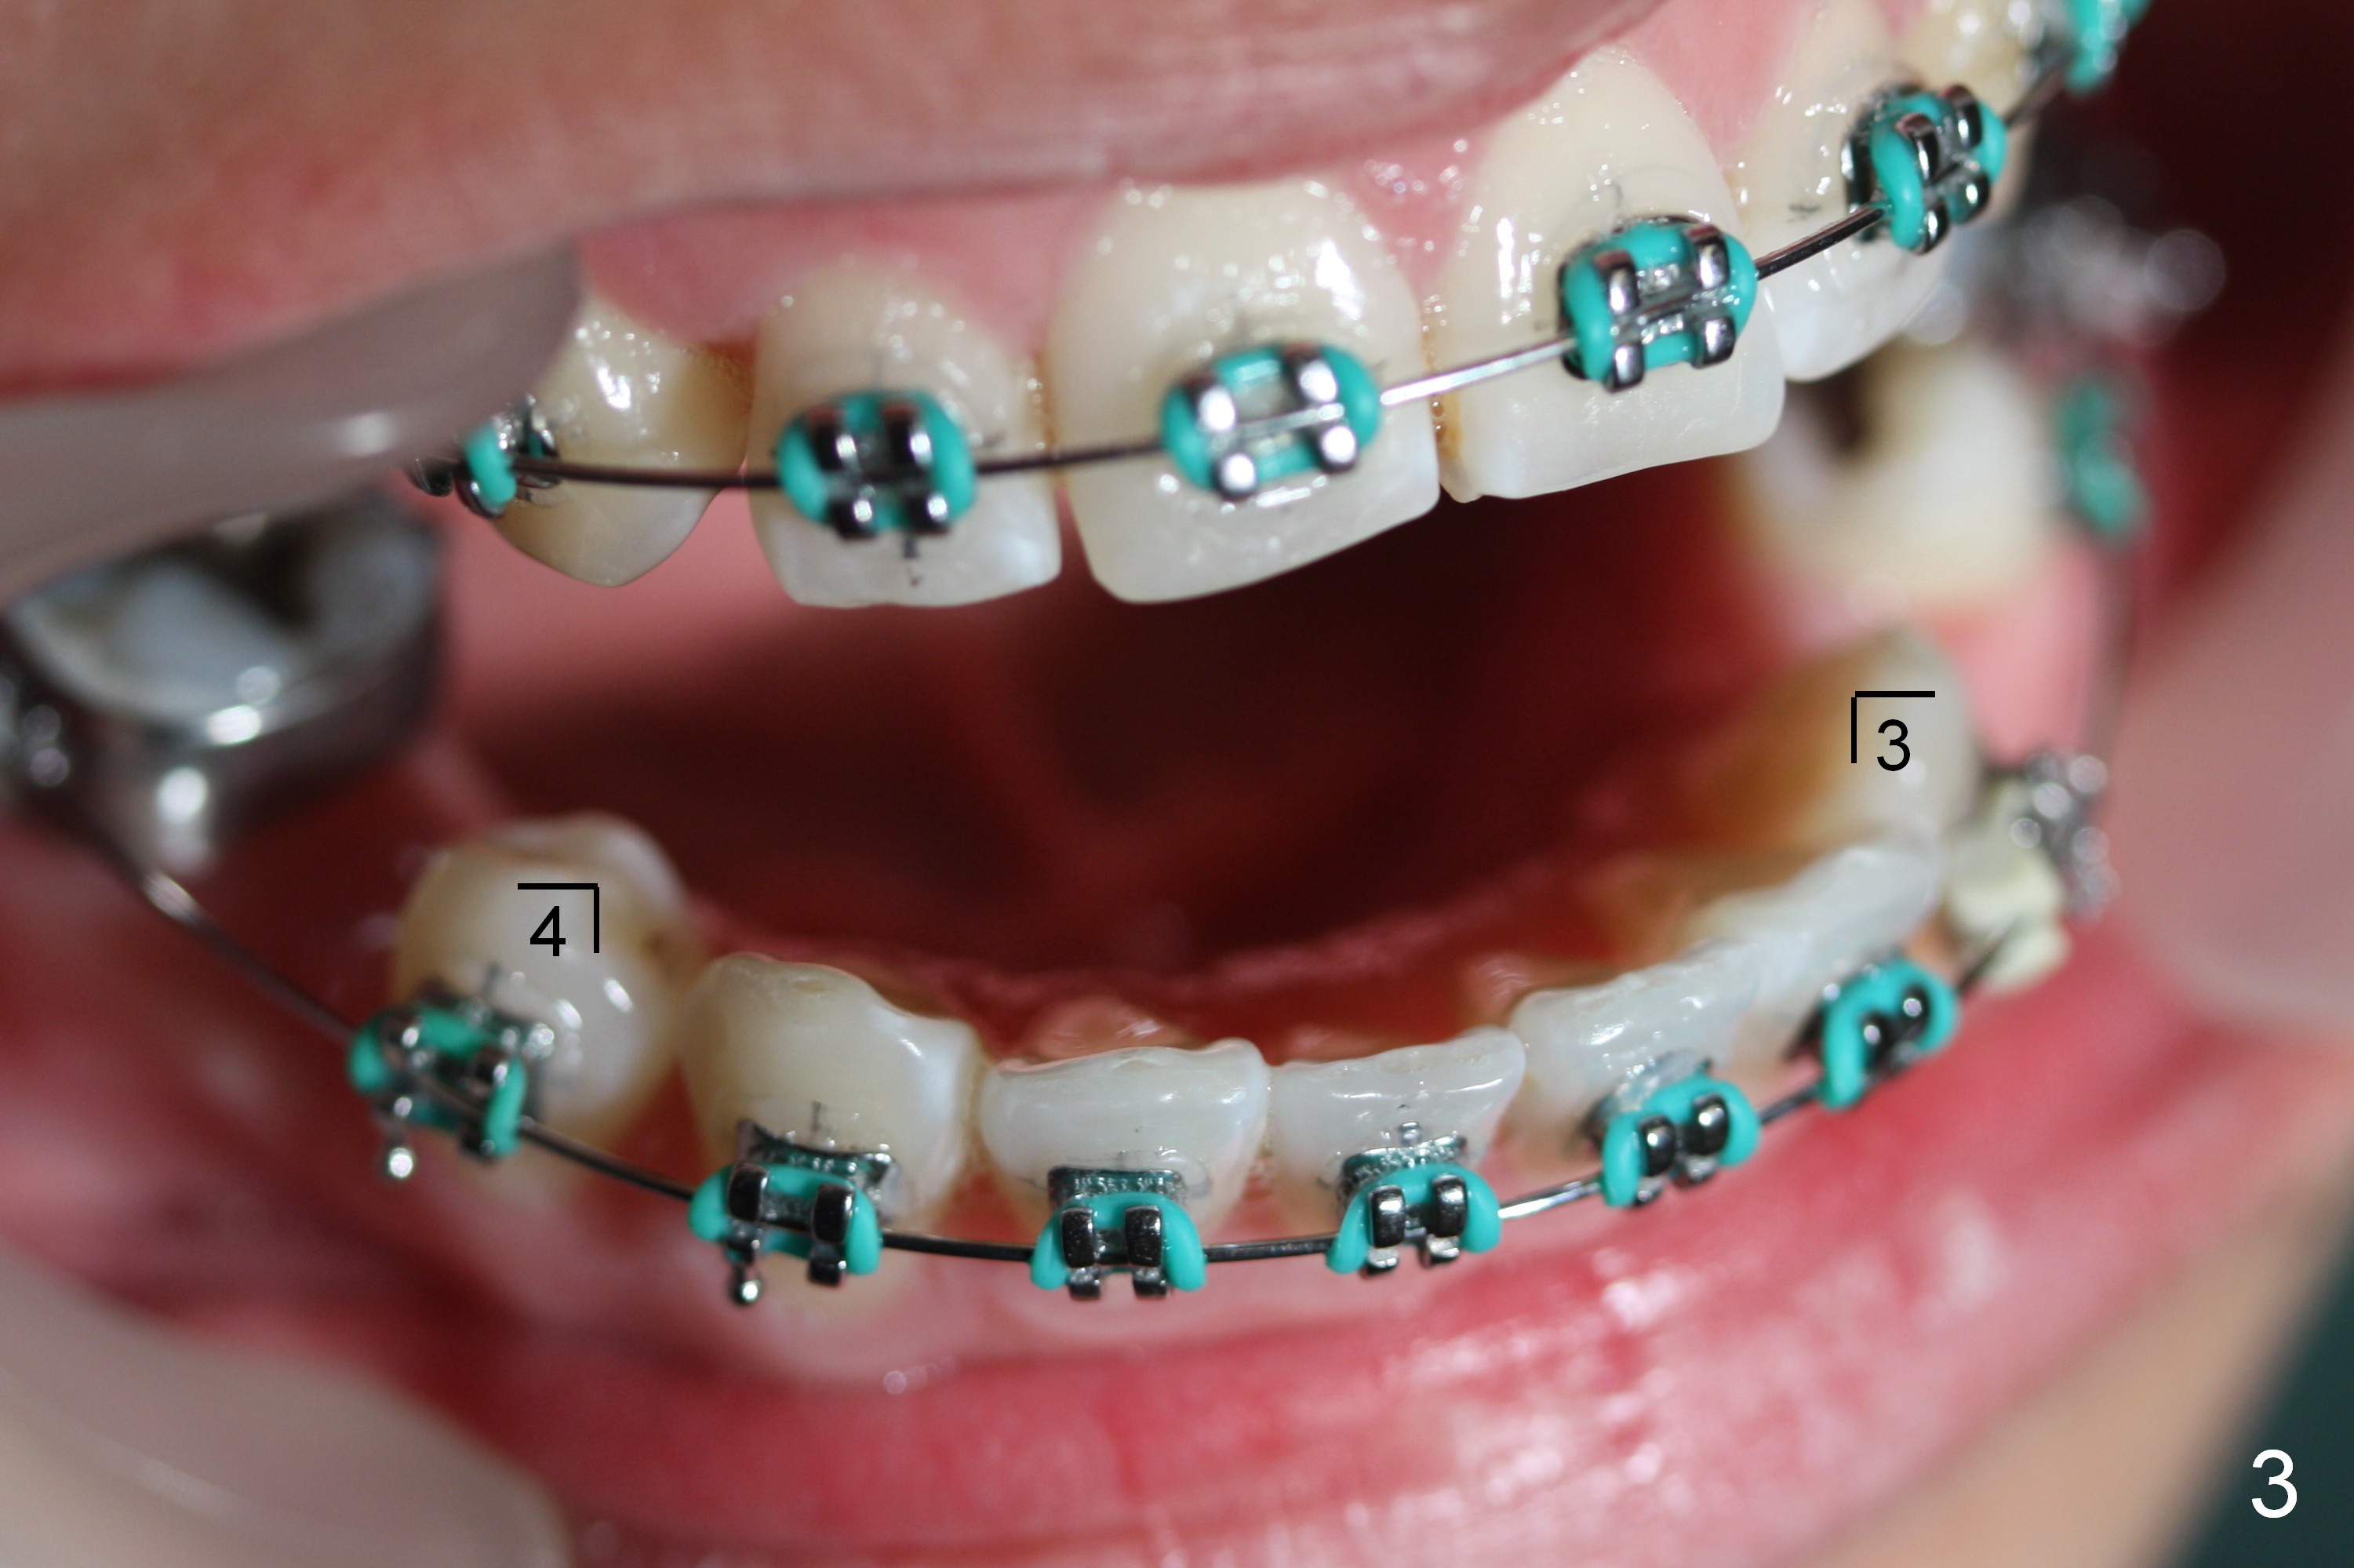

Three and a half months later, alignment improves (Fig.3-5). The present wires are .018" stainless steel (ss), which will be changed to .020" ss.

Next visit .016x.016" ss wires will be used. Two closed coil springs are placed between LR4 and 7 (Fig.4) and LL3 and 6 (Fig.5). The upper teeth will be retracted once the lower counterparts have achieved initial movement. Mini-implants are expected to be placed for upper retraction the following visit.